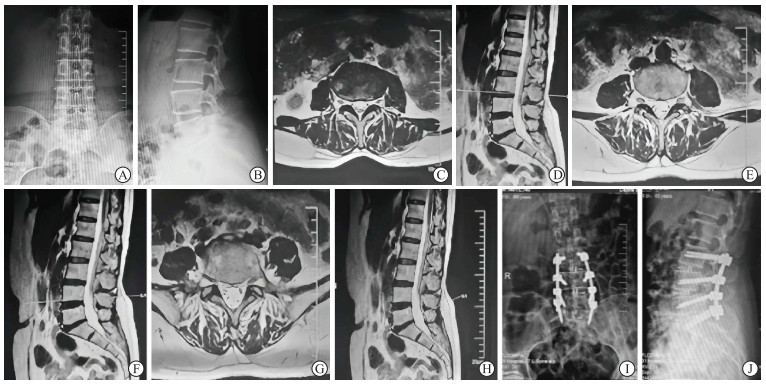

神经根型患者42例(男25例、女17例),平均年龄为(62.0±13.1)岁;椎间盘突出型73例(男42例、女31例),平均年龄为(63.5±14.5)岁;椎管狭窄型61例(男35例、女26例),平均年龄为(64.1±13.5)岁;滑脱型29例(男18例、女11例),平均年龄为(65.5±12.0)岁;局部型40例(男26例、女14例),平均年龄为(61.5±14.1)岁;合计男性LDD患者146例,女性患者99例,共245例,平均年龄为(62.9±13.8)岁。神经根型、椎间盘突出型、椎管狭窄型、滑脱型和局部型占比分别为17.14%、29.80%、24.90%、11.84%、16.33%。手术患者中单节段113例,双节段75例,3个及以上节段17例,非手术治疗40例。所有患者均获得随访,随访时间为(20.37±6.13)个月。典型神经根型LDD患者影像资料见图 2

图  2  神经根型LDD影像学表现

A 65-year-old female patient was admitted with a 2-year history of bilateral lower limb pain and numbness. The pain radiated from both buttocks to the posterior thighs and the posterolateral calves. Physical examination revealed bilateral lower limb muscle strength of grade Ⅳ and hyperactive tendon reflexes. Preoperative anteroposterior (A) and lateral (B) X-ray images indicated degenerative changes in the lumbar spine. MRI scans at L3/4 (C, D), L4/5 (E, F), and L5/S1 (G, H) in anteroposterior and lateral views showed no significant signs of nerve compression, but a positive cauda equina sedimentation sign was noted. The patient was diagnosed with nerve root type of LDD and underwent modified transforaminal lumbar interbody fusion surgery. Postoperative anteroposterior (I) and lateral (J) X-rays showed good implant positioning. Postoperatively, the lower limb symptoms were significantly relieved, and the muscle strength improved. LDD: Lumbar degenerative disease; MRI: Magnetic resonance imaging.